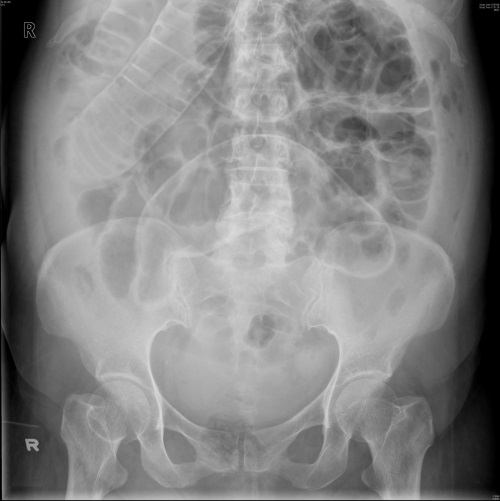

What does this AXR show?

It shows small bowel obstruction (valvulae conniventes) as well as a perforation (Rigler’s sign - you can see the bowel wall on both sides of the lumen).